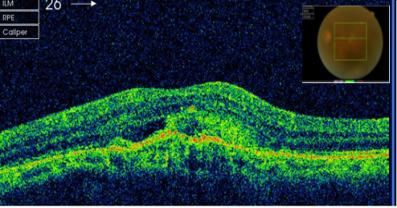

患者曹某,80岁,因双眼视力下降1年就诊。检查右眼视力0.3,左眼0.08,裂隙灯检查双眼晶体皮质混浊明显,散瞳后眼底检查见右眼黄斑区金箔样反光,左眼黄斑区中心凹反光消失。患者眼底荧光照影检查显示左眼黄斑区有血管荧光的渗漏,眼科光学相干断层扫描(OCT)检查显示右眼有黄斑前膜增生,左眼脉络膜新生血管膜(图片1)。诊断:左眼老年性黄斑变性(脉络膜新生血管),右眼黄斑前膜,双眼老年性白内障。患者于2013年3月行眼内注药(雷珠单抗)。3月后复诊左眼视力0.1,复查OCT示左眼视网膜新生血管膜消退(图片2),建议先行左眼白内障手术治疗。

图片1左眼:脉络膜新生血管膜